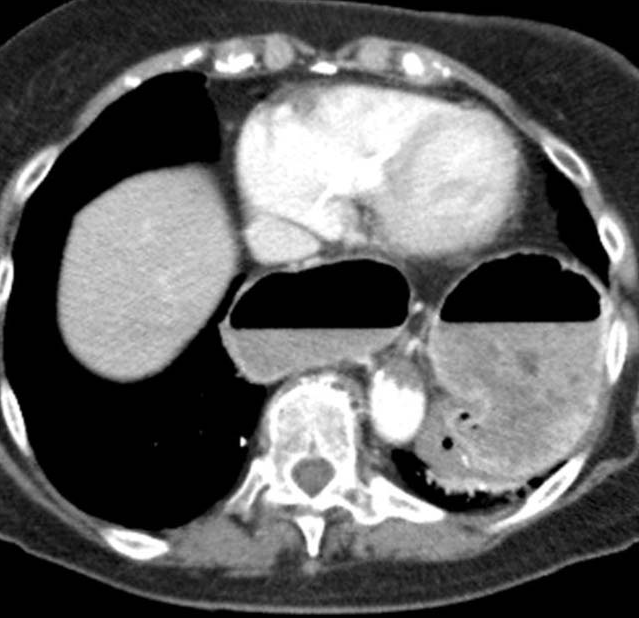

Abdominal computed tomography. Cystic lesion of the right lung. Courtesy Dr. V. Penopoulos.